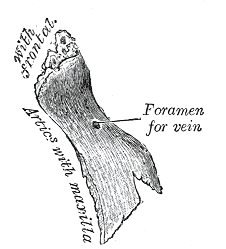

The outer surface is concavoconvex from above downward, convex from side to side; it is covered by the procerus and nasalis muscles, and perforated about its center by a foramen, for the transmission of a small vein.

Articulation of nasal and lacrimal bones with maxilla. Right nasal bone. Outer surface.

Right nasal bone. Outer surface. Right nasal bone. Inner surface.